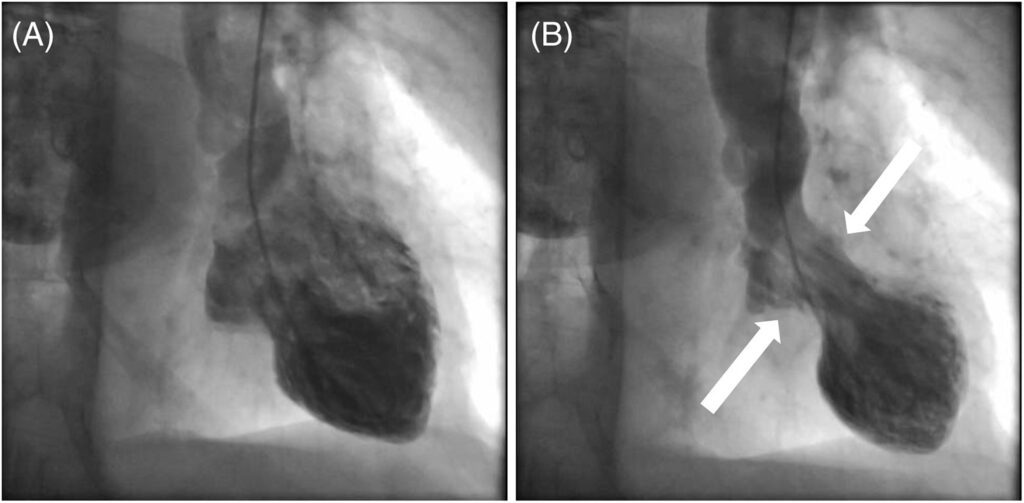

The condition’s name derives from the Japanese word “takotsubo,” meaning an octopus trap. This term mirrors the distinctive shape of the heart during this condition, resembling a pot used by fishermen to catch octopuses. Beyond its intriguing origin, this syndrome’s impact can be profound.

Apical: The most common type, affecting the lower half of the heart.